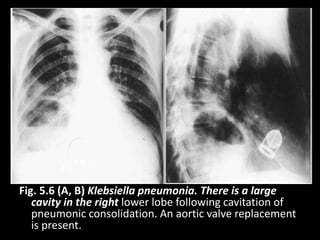

Fig. 5.6 (A, B) Klebsiella pneumonia. There is a large

cavity in the right lower lobe following cavitation of

pneumonic consolidation. An aortic valve replacement

is present.

Fig. 5.6 (A,B) Klebsiella pneumonia. There is a large cavity in the right lower lobe following cavitation of pneumonic consolidation. An aortic valve replacement is present.